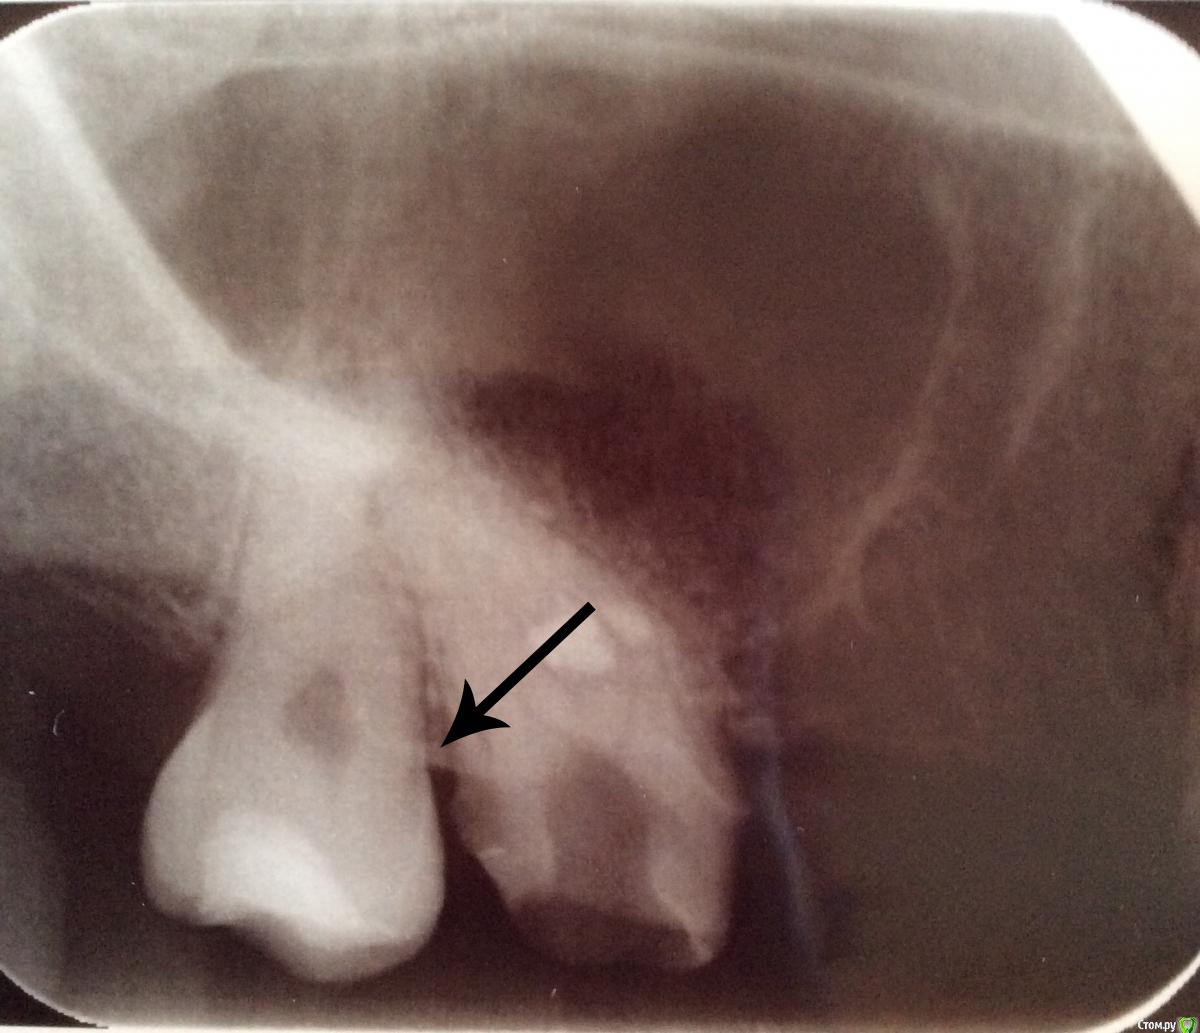

Natcar Опубликовано 19 июня, 2015 Поделиться Опубликовано 19 июня, 2015 (изменено) Здравствуйте. Я за помощью. Беспокоит зуб. Депульпировали под установку моста. Снимки до пломбировки каналов и после. Прошло 11дней. Боль при надавливании на мост имеено под этим зубом и переодически ноют нижние. (Мост Стоит на временном цементе, перестраховались) . Не могу сказать , что есть какаято нетерпимая боль, но опираясь на прошлый опыт страшновато. Очень не хочется потерять зуб. Так как подобная история была с соседним зубом (удалили после депульпирования). Спасибо всем кто откликнется! Изменено 19 июня, 2015 пользователем Natcar Ссылка на комментарий

Natcar Опубликовано 19 июня, 2015 Автор Поделиться Опубликовано 19 июня, 2015 Хорошо. Переделать получиться только в понедельник. А по этому снимку что то можно сказать? То, что выведен материал за верхушку -врач предупредила. (Поболит и перестанет) 5 дней физкотерапии прошла (лазер и увч) Ссылка на комментарий

Natcar Опубликовано 20 июня, 2015 Автор Поделиться Опубликовано 20 июня, 2015 Больше десяти лет назад был правосторонний гайморит. Затем наблюдалась у лора +профилактика . В диагнозе вазомоторный ринит. И в правой же пазухе по снимка были остатки пломбировочного материала или что-то в этом роде. Переодический насморк мой второй друг, и сильная заложенность при простуде и орви. Вторые сутки на ночь пью немисел , поэтому кажется что стало намного легче. Утром ощущения какбудто всю ночь сильно сдавливала зубы. Постараюсь сделать в ближайшие дни КТ. Ссылка на комментарий

Natcar Опубликовано 22 июня, 2015 Автор Поделиться Опубликовано 22 июня, 2015 Готово КТ , две ссылки на сайт файлообменника и облако майлруhttp://fayloobmennik.com/iir66p9dhmvl/0011.zip.htmlhttps://cloud.mail.ru/public/3UBG/8CR2mFiZW В клинике где делала снимок возникли вопросы по нижнему зубу -вроде как плохо запломбированный канал. У меня , кстати есть шишка при пульпации щеки на месте этого зуба. Беспокоит и может увеличиваться при простудах. Также слева сверху у семерки увидели незапломбированный канал. Хотя я в мае сходила на лечение в ходе которого мне установили на него коронку. Проблемы с зубом который меня беспокоит сейчас-ничего, кроме того, что много материала выведено за верхушку. В общем, растройстроена. Ссылка на комментарий